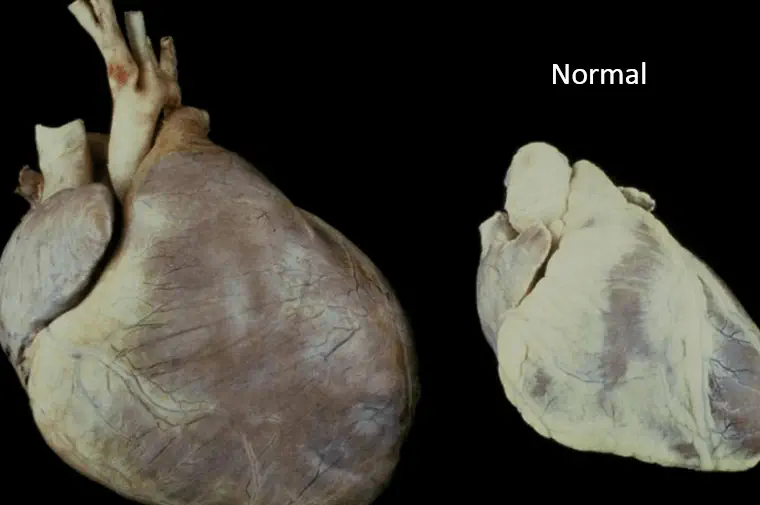

کاردیومیوپاتی (cardiomyopathy) عبارت است از: ضخیم شدن و سفت شدن عضله (ماهیچه) قلب. مراحل ا...

نقص (نارسایی) مادرزادی قلب (نقص قلبی که از زمان تولد ایجاد میشود)، اگر جدی باشد، در همان ...